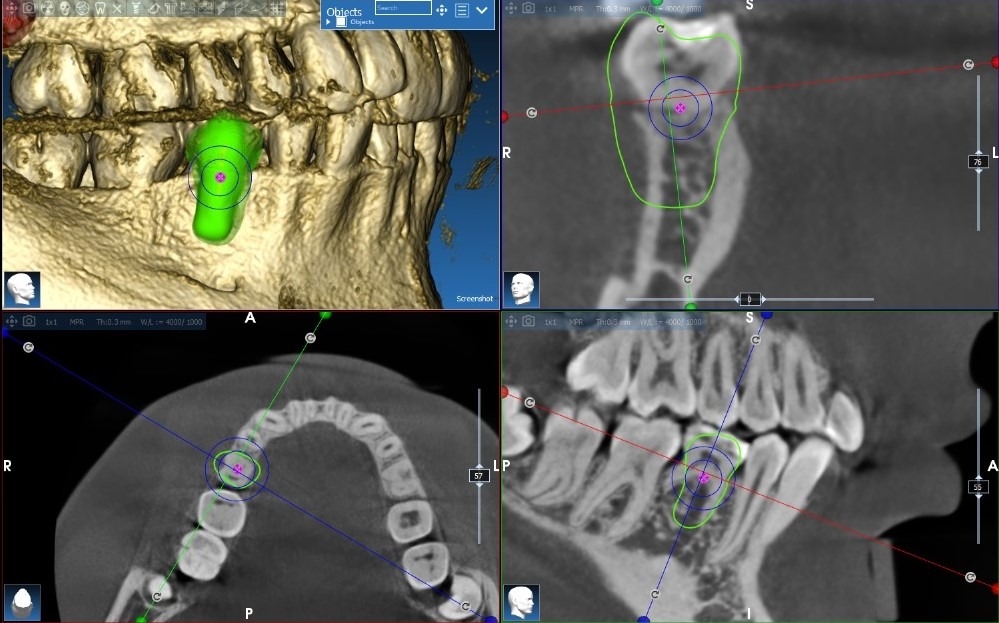

Single Implant with Bone Graft

Guided implant placement with simultaneous bone augmentation